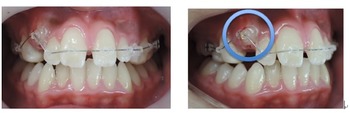

治療は上顎から矯正装置を装着していきます。その後下顎の矯正装置を装着します。

この過程で歯並びが整いMEAW(マルチループ)を装着しやすくなります。

MEAW(マルチループ)を使用する事で顎偏位により左右の咬合高径(咬み合わせの高さ)の改善をしています。その治療により左右の顎のズレが改善されます。

(症例一口メモ)

顎偏位は上顎前突や下顎前突のように顎骨の前後のズレではなく左右のズレである為に歯を抜いて治療する事が出来ないストレートワイヤー法では治療が困難な症例です。

当院はMEAW(マルチループ)により効率的に治療を進めています。